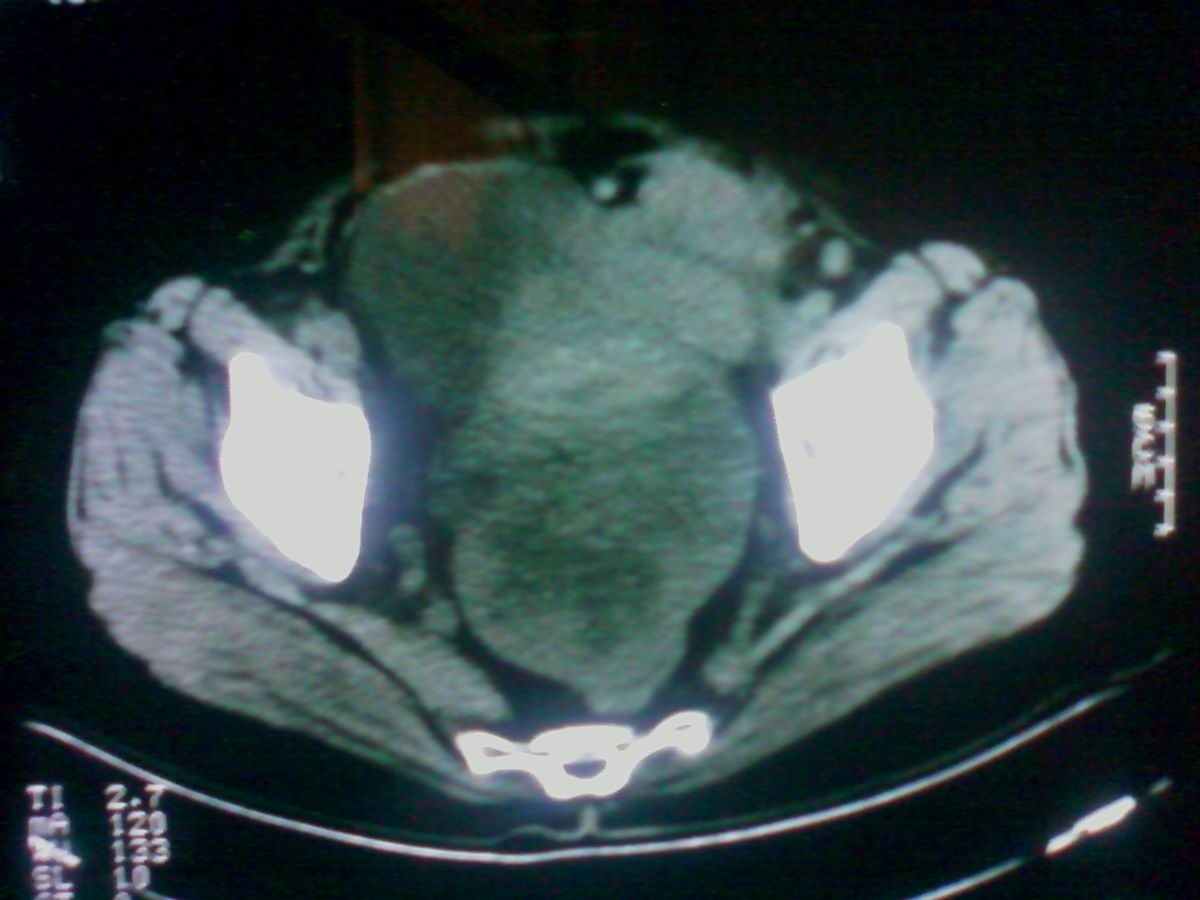

标题: CT25799:女性患者,45岁,腹胀,上腹部疼痛来诊,B超示盆腔 [打印本页]

标题: CT25799:女性患者,45岁,腹胀,上腹部疼痛来诊,B超示盆腔

考虑卵巢癌伴腹水

1)考虑卵巢恶性肿瘤。2)腹水。